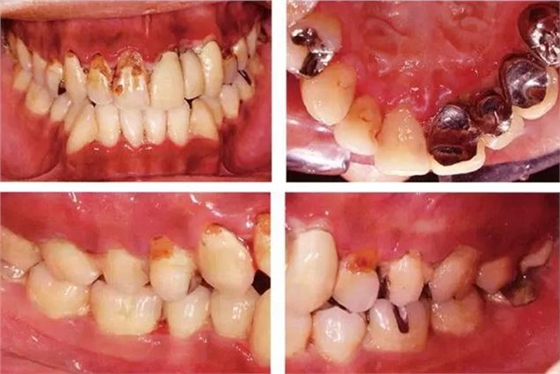

●33歲男性 侵襲性牙周炎廣泛型口腔內(nèi)照片

33歲男性,吸煙(1天10根,12年吸煙史)。菌斑控制狀況不好,牙周探診全頜牙周袋深5~10mm之外,全頜性牙周袋出血,部分牙周袋有排膿現(xiàn)象。X片可觀察到全頜性重度骨吸收。通過以上檢查可診斷出該患者為侵襲性牙周炎廣泛型。視診可知牙齦雖然有炎癥,但沒有出現(xiàn)嚴(yán)重浮腫,沒有大量牙結(jié)石沉積。